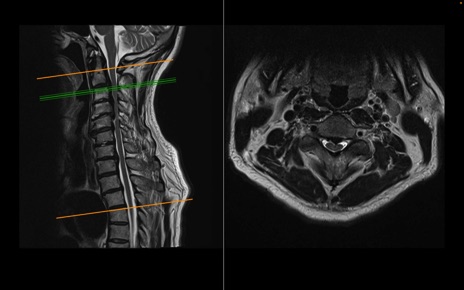

頚椎MRI

T2WI(横断像)

T2WI(矢状断像)